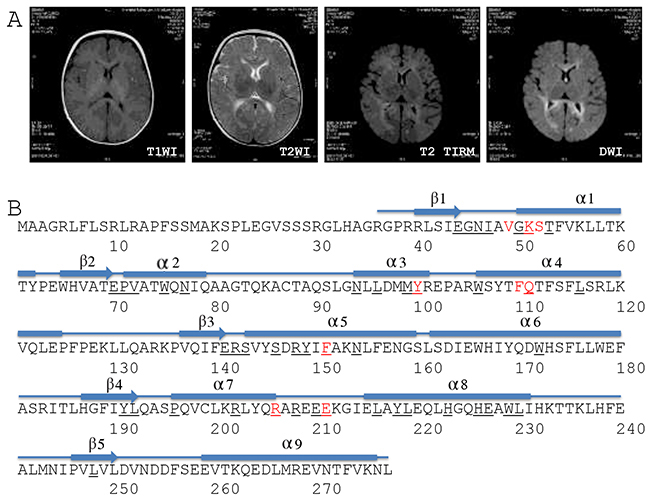

Abdominal ultrasonography showed multiple focal liver lesions, hepatic fibrosis, and massive ascites. Brain magnetic resonance imaging (MRI) showed higher DWI and T2WI signals in the bilateral frontal, temporal, parietal, and occipital lobes, the corpus callosum, internal and external capsules, and the brain stem (Figure 1A). In addition, a high T2WI signal also was observed in the bilateral globus pallidus (Figure 1A). Proton magnetic resonance spectroscopic imaging showed normal N-acetylaspartate, choline and creatine peaks in the basal ganglia and thalamus. The results suggested that the patient had hepatocerebral MDS and was thus given symptomatic and supportive treatment for eight days in our hospital. The girl died one and a half months after release from the hospital.

Figure 1: Brain MRI and DGUOK structure. (A) Brain MRI. T1WI, T1 weighted image; T2WI, T2 weighted image; TIRM, turbo inversion recovery magnitude; DWI, diffusion-weighted magnetic resonance imaging. (B) Structure-based sequence alignment of the human DGUOK gene (SwissProt Q16854). The numbers refer to the DGUOK amino acid sequence. Red characters refer to the conserved substrate-binding site. Black fields represent residues identical to the sequences of deoxycytidine kinase, thymidine kinase 2, and deoxyribonucleoside kinase.

Genetic testing revealed that this girl was a compound heterozygote for DGUOK gene alleles c.128T>C (p.I43T) and c.313C>T (p.R105*) (Table 2). Her father was a heterozygous carrier of allele c.128T>C (p.I43T). c.128T>C (p.I43T), a novel variant located in exon 1 (National Center for Biotechnology Information ID: NM_080916) that encoded an amino acid in the first beta sheet of the DGUOK protein (Table 2 and Figure 1B). c.128T>C (p.I43T) has been included in the Human Gene Mutation Database, the NHLBI GO Exome Sequencing Project, or the 1000 Genomes Project to date, and has not been previously reported (Table 2). The patient’s mother was a heterozygous carrier of allele c.313C>T (p.R105*). c.313C>T (p.R105*) is located in exon 2 (NM_080916) and encodes amino acids located in the third and fourth alpha helixes of the DGUOK protein (Table 2 and Figure 1B). c.313C>T (p.R105*) is predicted to result in a 173 amino acid residue truncation at the C terminus of the DGUOK protein [18]. No prior cases of MDS were found in the family histories of either parent.

The DGUOK protein consists of five beta sheets and nine alpha helixes (Figure 1B) [32]. Nine amino acids make up a conserved substrate-binding site, and 45 amino acids are identical to deoxycytidine kinase, thymidine kinase 2, and deoxyribonucleoside kinase (Figure 1B) [32]. Although previous reports have shown that some variants change highly conserved amino acids [3, 4, 9, 16, 20, 23], integrated data show that mutations are not confined to these conserved sites. Many variants occur outside of the conserved region [3-9, 11-13, 19, 21, 25, 27, 30].